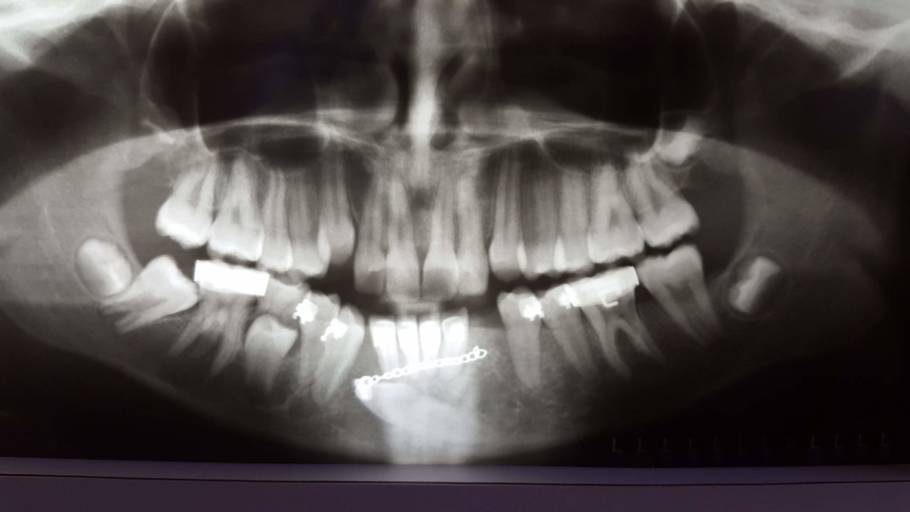

You are a great candidate for orthodontic treatment.  It appears that your maxillary (upper) teeth are slightly flared, bringing these teeth back into proper alignment will close the space between your maxillary and mandibular front teeth.  In the bottom right picture, it is hard to see if your posterior (back) teeth are touching.  If they are, then you are considered to have an "open" bite.  Your upper front teeth should slightly overlap your lower front teeth allowing you to bite into and tear your foods easily.  More than likely, the orthodontist will recommend a full orthodontic treatment case placing you in treatment for 12-18 months, followed by retention.